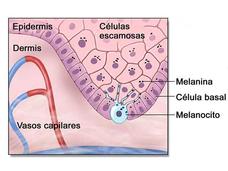

La FDA aprueba el sonidegib para algunos pacientes con carcinoma avanzado de células basales

La FDA ha aprobado sonidegib para el tratamiento de pacientes con carcinoma de células basales localmente avanzado